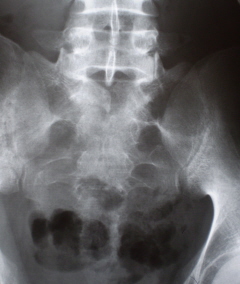

Произведена рентгенография таза. На обзорной рентгенограмме таза (иллюстрация № 6)

6

имеет место незаращение дужки 1 крестцового позвонка. Определяется остеопороз в девой половине крестца, преимущественно на уровне 1 и 2 крестцовых позвонков. Местами костные трабекулы вообще не дифференцируются. Произведено томографическое исследование – иллюстрации в прикрепленном файле.

Иллюстрация 4 – фрагмент зоны остеопороза.

Иллюстрация 5 – «патологический процесс» в виде участка деструкции костной ткани «захватывает» левую половину крестца на уровне 1,2 и частично 3 позвонков, основание верхнего суставного отростка, местами с полным «лизисом» костной ткани.